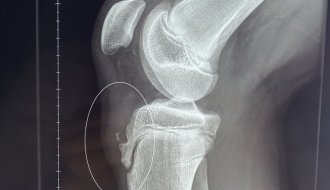

Эффективное лечение болезни Шляттера ударно-волновой терапией (УВТ) в Киеве в мед центре «Аватаж»

Когда ребенок-спортсмен жалуется на постоянную боль под коленом, и при этом он активно растет, то это может быть болезнь Шляттера. Обычно ее страдают подростки, особенно мальчики 10-16 лет, которые совмещают интенсивные тренировки